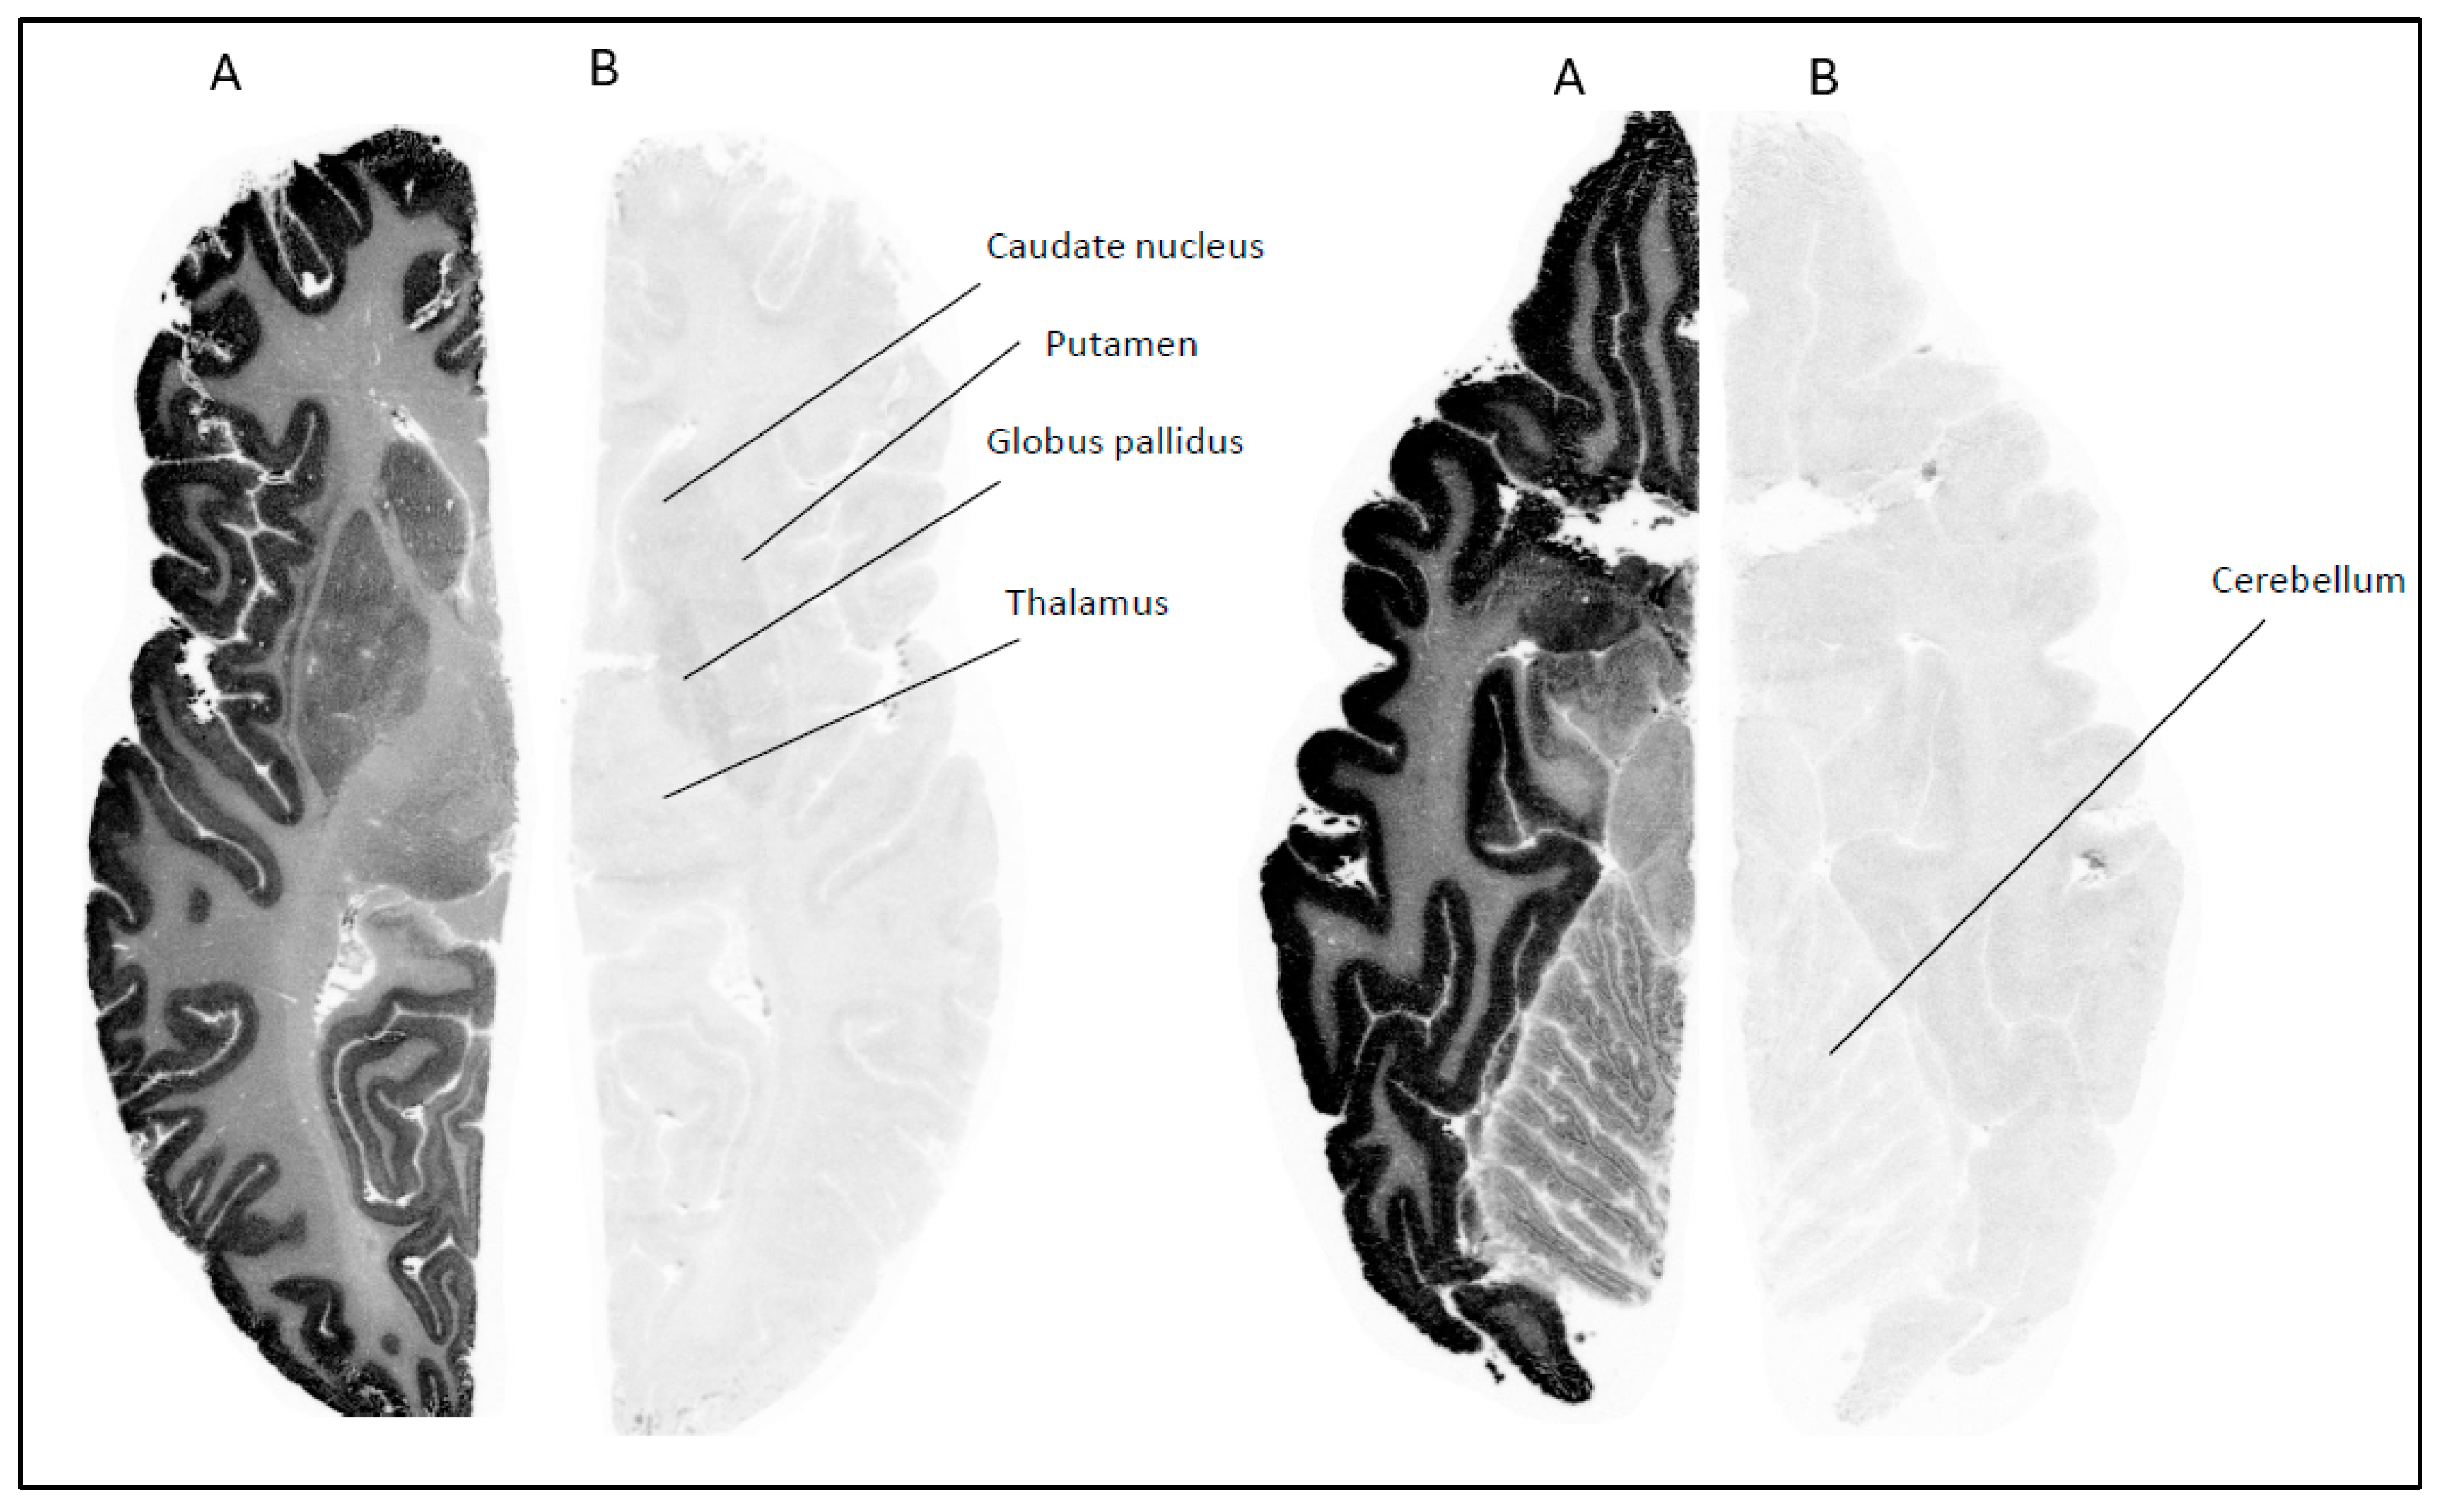

Figure 2. Autoradiograms of sagittal slices of a NHP brain labeled with [18F]1 at baseline condition (A) and during incubation with cold Compound 1 (10 µM) (B) and Compound 3 (10 µM) (C).

The in vitro ARG studies aimed to assess the binding characteristics of the compounds; [18F]1 displayed clear binding in brain slices from NHP (Figure 2) and human (Figure 3). The binding was effectively blocked by an excess of cold Compound 1 (self-block) as well as Compound 3 (heterologous block), indicating that its interaction with brain tissue is likely specific. However, pre-incubation with 0.1 µM of PFE-360 [20], another structurally different LRRK2 kinase inhibitor, did not significantly reduce the binding of [18F]1 in a human brain slice (Figure 4). This could indicate that [18F]1 exhibited limited specificity but more likely that the concentration of PFE-360 used may have been suboptimal, as Compound 2 demonstrated significant blocking activity at 10 µM.